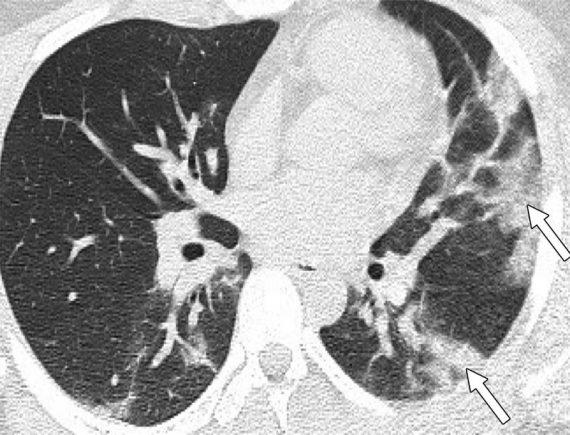

Μία εικόνα χίλιες λέξεις. Αξονικές τομογραφίες νέων κάτω από 18 έτη με Covid-19 (18 ετών, 15 ετών, 14 ετών και 8 ετών). Κανένας ασθενής δεν είχε υποκείμενα νοσήματα ή ανοσοκαταστολή. Οι ασθενείς δεν χρειάστηκαν συμπληρωματικό οξυγόνο, διασωλήνωση ή ΜΕΘ. Πρόκειται για απλά-κοινά περιστατικά Covid-19.

Ωστόσο έχουν πολύ “εντυπωσιακές” βλάβες και είναι άγνωστο τι θα προκαλέσουν αυτές οι βλάβες σε βάθος χρόνου. Για την πλειονότητα του κόσμου το ερώτημα είναι απλό: Θέλουν να υποβάλουν τους πνεύμονές τους σε αυτές τις βλάβες για να δουν αν αντέχουν; Και αν αντέξουν την πρόκληση (όπως προβλέπεται ότι θα αντέξουν οι περισσότεροι νέοι) θέλουν να δουν πόσα χρόνια ή αντοχές έχασαν στην πορεία; Με το εμβόλιο προστατεύουμε τους πνεύμονές μας από βαρύτατη καταπόνηση!